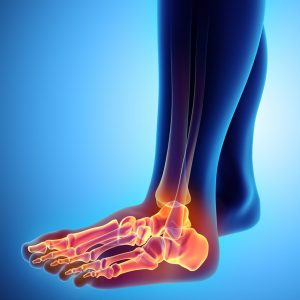

С пролотерапия можете да лекувате болка и артрит, идващи от раменете, лактите, китките и ръцете, бедрата и коленете, глезена и крака и дори челюстта.

Понякога лигаментите могат да бъдат пренатягани или дори разкъсани (както при изкълчен глезен). Лигаментът може след това да не контролира адекватно ставата – това води до „нестабилност“, която може да постави ненормални натоварвания върху ставите и дисковете в гръбначния стълб. Нестабилността се усложнява от срив в стабилизиращата мускулна система чрез мускулна слабост, умора и лоша координация.